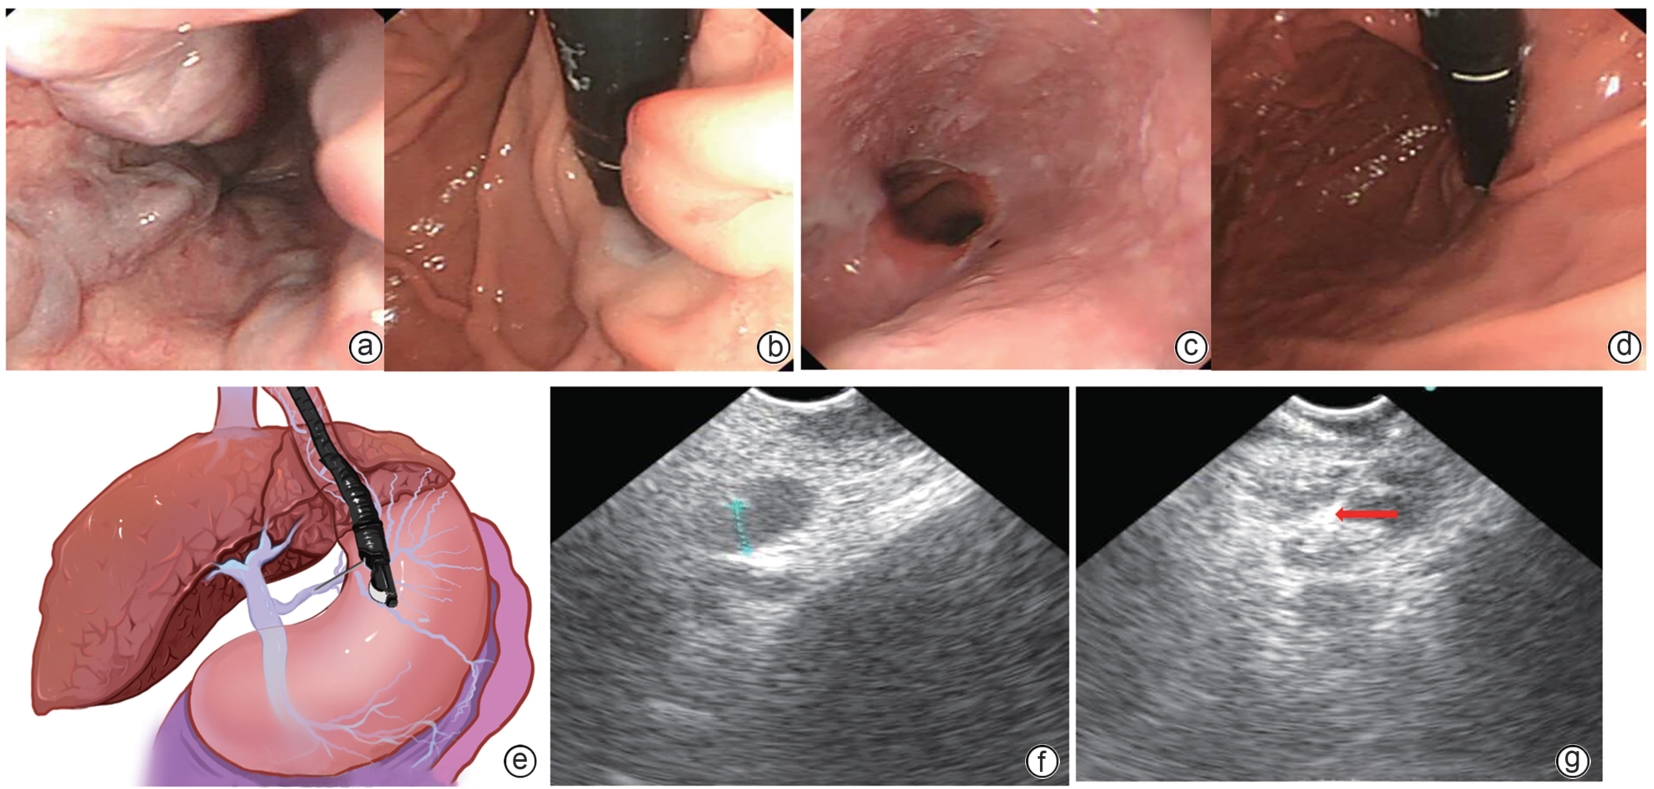

Safety and efficacy of puncture cyanoacrylate selective seal under endoscopic ultrasound versus traditional endoscopy in treatment of gastroesophageal varices: A randomized controlled trial

Jiali MA, Lingling HE, Hongshan WEI, Ping LI, Xiuxia LIANG

2025, 41(6): 1113-1119. DOI: 10.12449/JCH250617

Abstract(1013) HTML (176) PDF (1855KB)(56)

Abstract:

Objective  To investigate the safety and efficacy of puncture cyanoacrylate selective seal (PCSS) under endoscopic ultrasound in the treatment of gastroesophageal varices (GOV).  Methods  A total of 100 patients with liver cirrhosis who underwent endoscopic therapy for the secondary prevention of GOV bleeding in Beijing Ditan Hospital, Capital Medical University, from March 1 to December 31, 2023 were enrolled and randomly divided into PCSS group and traditional endoscopy group. The patients were followed up for 6 months after surgery, and the two groups were compared in terms of clinical outcome and complications. The primary outcome measure was the rate of alleviation or disappearance of GOV, and the secondary outcome measure was variceal rebleeding and death. The independent-samples t test was used for comparison of normally distributed or approximately normally distributed quantitative data between two groups, and the Wilcoxon non-parametric test was used for comparison of non-normally distributed quantitative data between two groups; the chi-square test or the Fisher’s exact test was used for comparison of qualitative data between two groups.  Results  There were 50 patients in the PCSS group, among whom 1 patient was lost to follow-up, and there were 50 patients in the traditional endoscopy group, among whom 3 patients were lost to follow-up. There were no significant differences between the two groups in baseline data such as age, sex, Child-Pugh class, varices grade, and GOV typing (all P>0.05). Compared with the traditional endoscopy group, the PCSS group had significantly better results of the number of endoscopic treatment sessions (t=-15.671, P=0.001), the total amount of tissue adhesive used (t=-2.830, P=0.006), and the rate of alleviation or eradication of varices sclerosis (χ2=7.078, P=0.029). Both groups had low rates of postoperative rebleeding, adverse reactions, and complications, and there were no significant differences between the two groups (all P>0.05).  Conclusion  Compared with traditional endoscopy, PCSS can significantly enhance treatment outcome while maintaining safety standards.